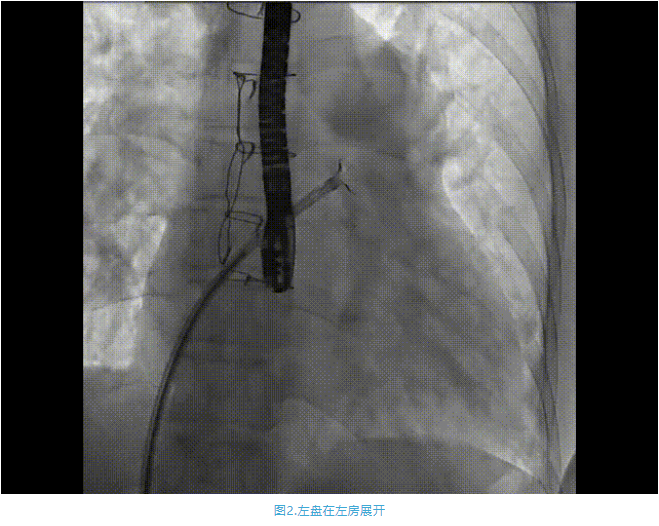

術(shù)中首先在局麻下穿刺股動(dòng)脈、股靜脈,完成心導(dǎo)管檢查評(píng)估后轉(zhuǎn)為全麻,在食道超聲引導(dǎo)下穿刺房間隔,穿刺成功后將加硬導(dǎo)絲送入左上肺靜脈建立軌道,根據(jù)患者病情行球囊預(yù)擴(kuò)張后植入6mm孔徑房間隔造孔支架,經(jīng)透視及食道超聲評(píng)估支架左右盤展開良好,夾持于房間隔兩側(cè),固定穩(wěn)定、位置良好,食道彩超顯示房水平右向左為主分流,分流孔直徑符合預(yù)期大小,心導(dǎo)管檢查評(píng)估達(dá)到預(yù)期效果,釋放造孔支架。術(shù)后12h患者下床活動(dòng),恢復(fù)順利,擬于近日完善術(shù)后評(píng)估后出院。